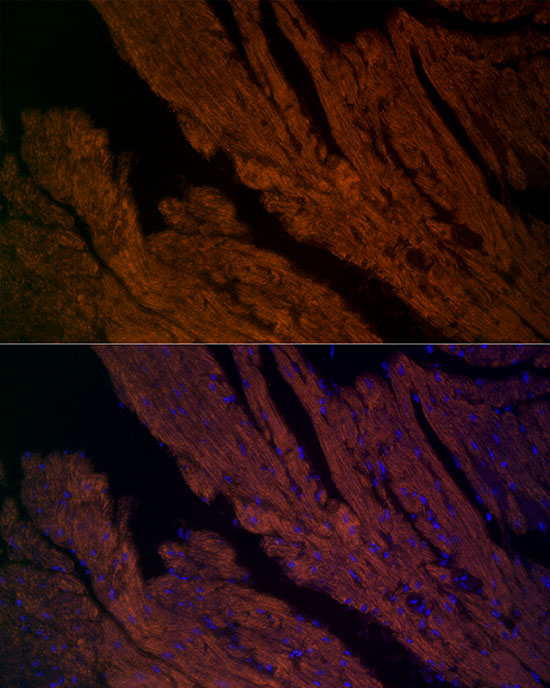

Western blot analysis of extracts of Mouse heart, using RYR2 antibody at 1:710 dilution.

Secondary antibody: HRP Goat Anti-Rabbit IgG at 1:10000 dilution.

Lysates/proteins: 25ug per lane.

Blocking buffer: 3% nonfat dry milk in TBST.

Detection: ECL Basic Kit .

Exposure time: 30s.